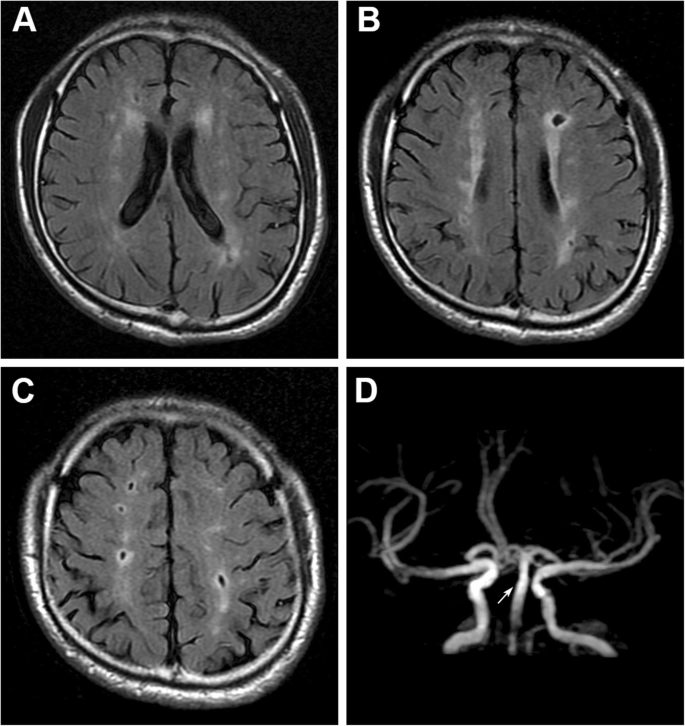

其实腔梗只是一个缩写 , 它的全名是腔隙性脑梗死 , 这种脑梗死的本质 , 其实是大脑血管中小动脉的闭塞而出现的脑组织损伤 。

一般来说范围在1.5厘米-2厘米之间 , 这个范围 , 我们都称之为腔隙性脑梗死 。

特别是在之后复查的影像学检查中 , 比如CT和核磁当中可以看到梗死之后的地方成为了一个天然的腔隙 , 所以因此得名腔隙性脑梗死 。